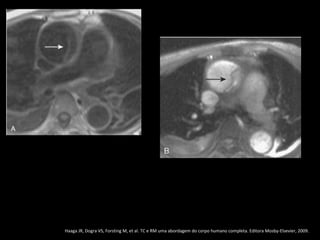

RM: T1 com gadolínio.

Pseudoaneurisma crônico

Haaga JR, Dogra VS, Forsting M, et al. TC e RM uma abordagem do corpo humano completa. Editora Mosby-Elsevier, 2009.

Trauma torácico: coice de um cavalo

RM: T1 comgadolínio. Pseudoaneurisma crônico Haaga JR, Dogra VS, Forsting M, et al. TC e RM uma abordagem do corpo humano completa. Editora Mosby-Elsevier, 2009.

Trauma torácico: coicede um cavalo Haaga JR, Dogra VS, Forsting M, et al. TC e RM uma abordagem do corpo humano completa. Editora Mosby-Elsevier, 2009.

História remota deacidente automotor Haaga JR, Dogra VS, Forsting M, et al. TC e RM uma abordagem do corpo humano completa. Editora Mosby-Elsevier, 2009.